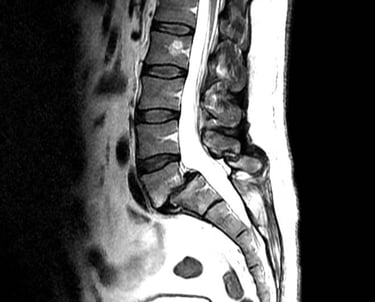

Columna lumbar

Ciática.

Lumbalgia.

Hernias de disco intervertebral.

Espondilolísis.

Espondilolistésis

Escoliosis.

Tumores de columna lumbar.

Escoliosis degenerativa del adulto mayor.

Fracturas traumáticas y patológicas.